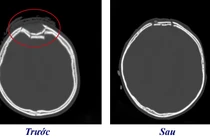

(khoahocdoisong.vn) - Nhờ kích hoạt báo động đỏ huy động lực lượng các chuyên khoa và phòng mổ thông minh hàng đầu châu Á, các bác sĩ Bệnh viện Bãi Cháy (Quảng Ninh) đã tận dụng “thời gian vàng” để cứu sống bệnh nhân vỡ hộp sọ phức tạp, tổn thương não nặng, lóc toàn bộ da đầu... do kẹp thang máy.